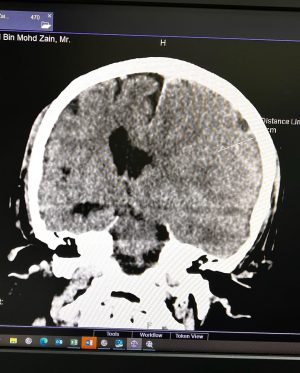

Caption : Kalau anyone you know jatuh kepala terhentak, luaran memang takde apa tapi dalaman maybe boleh jadi pendarahan perlahan. Sejurus dari terjatuh, bila check X-Ray dan CT scan it will tell you nothing, semua clear saja, but 2-3weeks later could turn into your biggest nightmare when the blood has flooded a big part of your brain. My dad realised something was wrong hampir sebulan lepas jatuh, when suddenly he couldn’t really move his right leg. Macam lagging. Sebab dia jatuh terhentak dahi kiri, bila anggota belah kanan yang terjejas, we knew it must be the brain. I picked him up and asked about his very very recent trip to Acheh, he said “Bila Daddy pergi Acheh?”. Ya Allah this very man, is my dad, someone who was very sharp and opinionated, tiba-tiba sangat blur dan slow, jawab sepatah-sepatah. So I spent the whole day uruskan dia, consulted two specialists and one neurosurgeon and when he is finally admitted that night to prepare him for his surgery the following day, he told the family “Daddy tadi drive sendiri datang sini”. My heart sank, I was frantic with worry — takutnya lagi lambat ni lagi banyak memori dia hilang. The brain surgery went well atas izin Allah, thank you to everyone involved. Doktor kata kalau lewat sikit je lagi memang boleh hilang keupayaan bercakap, keupayaan bernafas dan seterusnya koma, sebab otak dah compressed terlalu banyak darah. I jot this here as a reminder for all of us to always jangan tangguh-tangguh kalau hati dah tergerak. Daddy masih tak ingat I bawak dia pi hospital hari tu. Nasib baik kita selfie.Likes : 168141

Caption : Kalau anyone you know jatuh kepala terhentak, luaran memang takde apa tapi dalaman maybe boleh jadi pendarahan perlahan. Sejurus dari terjatuh, bila check X-Ray dan CT scan it will tell you nothing, semua clear saja, but 2-3weeks later could turn into your biggest nightmare when the blood has flooded a big part of your brain. My dad realised something was wrong hampir sebulan lepas jatuh, when suddenly he couldn’t really move his right leg. Macam lagging. Sebab dia jatuh terhentak dahi kiri, bila anggota belah kanan yang terjejas, we knew it must be the brain. I picked him up and asked about his very very recent trip to Acheh, he said “Bila Daddy pergi Acheh?”. Ya Allah this very man, is my dad, someone who was very sharp and opinionated, tiba-tiba sangat blur dan slow, jawab sepatah-sepatah. So I spent the whole day uruskan dia, consulted two specialists and one neurosurgeon and when he is finally admitted that night to prepare him for his surgery the following day, he told the family “Daddy tadi drive sendiri datang sini”. My heart sank, I was frantic with worry — takutnya lagi lambat ni lagi banyak memori dia hilang. The brain surgery went well atas izin Allah, thank you to everyone involved. Doktor kata kalau lewat sikit je lagi memang boleh hilang keupayaan bercakap, keupayaan bernafas dan seterusnya koma, sebab otak dah compressed terlalu banyak darah. I jot this here as a reminder for all of us to always jangan tangguh-tangguh kalau hati dah tergerak. Daddy masih tak ingat I bawak dia pi hospital hari tu. Nasib baik kita selfie.Likes : 168141

Caption : Kalau anyone you know jatuh kepala terhentak, luaran memang takde apa tapi dalaman maybe boleh jadi pendarahan perlahan. Sejurus dari terjatuh, bila check X-Ray dan CT scan it will tell you nothing, semua clear saja, but 2-3weeks later could turn into your biggest nightmare when the blood has flooded a big part of your brain. My dad realised something was wrong hampir sebulan lepas jatuh, when suddenly he couldn’t really move his right leg. Macam lagging. Sebab dia jatuh terhentak dahi kiri, bila anggota belah kanan yang terjejas, we knew it must be the brain. I picked him up and asked about his very very recent trip to Acheh, he said “Bila Daddy pergi Acheh?”. Ya Allah this very man, is my dad, someone who was very sharp and opinionated, tiba-tiba sangat blur dan slow, jawab sepatah-sepatah. So I spent the whole day uruskan dia, consulted two specialists and one neurosurgeon and when he is finally admitted that night to prepare him for his surgery the following day, he told the family “Daddy tadi drive sendiri datang sini”. My heart sank, I was frantic with worry — takutnya lagi lambat ni lagi banyak memori dia hilang. The brain surgery went well atas izin Allah, thank you to everyone involved. Doktor kata kalau lewat sikit je lagi memang boleh hilang keupayaan bercakap, keupayaan bernafas dan seterusnya koma, sebab otak dah compressed terlalu banyak darah. I jot this here as a reminder for all of us to always jangan tangguh-tangguh kalau hati dah tergerak. Daddy masih tak ingat I bawak dia pi hospital hari tu. Nasib baik kita selfie.Likes : 168141

Caption : Kalau anyone you know jatuh kepala terhentak, luaran memang takde apa tapi dalaman maybe boleh jadi pendarahan perlahan. Sejurus dari terjatuh, bila check X-Ray dan CT scan it will tell you nothing, semua clear saja, but 2-3weeks later could turn into your biggest nightmare when the blood has flooded a big part of your brain. My dad realised something was wrong hampir sebulan lepas jatuh, when suddenly he couldn’t really move his right leg. Macam lagging. Sebab dia jatuh terhentak dahi kiri, bila anggota belah kanan yang terjejas, we knew it must be the brain. I picked him up and asked about his very very recent trip to Acheh, he said “Bila Daddy pergi Acheh?”. Ya Allah this very man, is my dad, someone who was very sharp and opinionated, tiba-tiba sangat blur dan slow, jawab sepatah-sepatah. So I spent the whole day uruskan dia, consulted two specialists and one neurosurgeon and when he is finally admitted that night to prepare him for his surgery the following day, he told the family “Daddy tadi drive sendiri datang sini”. My heart sank, I was frantic with worry — takutnya lagi lambat ni lagi banyak memori dia hilang. The brain surgery went well atas izin Allah, thank you to everyone involved. Doktor kata kalau lewat sikit je lagi memang boleh hilang keupayaan bercakap, keupayaan bernafas dan seterusnya koma, sebab otak dah compressed terlalu banyak darah. I jot this here as a reminder for all of us to always jangan tangguh-tangguh kalau hati dah tergerak. Daddy masih tak ingat I bawak dia pi hospital hari tu. Nasib baik kita selfie.Likes : 168141

Caption : Kalau anyone you know jatuh kepala terhentak, luaran memang takde apa tapi dalaman maybe boleh jadi pendarahan perlahan. Sejurus dari terjatuh, bila check X-Ray dan CT scan it will tell you nothing, semua clear saja, but 2-3weeks later could turn into your biggest nightmare when the blood has flooded a big part of your brain. My dad realised something was wrong hampir sebulan lepas jatuh, when suddenly he couldn’t really move his right leg. Macam lagging. Sebab dia jatuh terhentak dahi kiri, bila anggota belah kanan yang terjejas, we knew it must be the brain. I picked him up and asked about his very very recent trip to Acheh, he said “Bila Daddy pergi Acheh?”. Ya Allah this very man, is my dad, someone who was very sharp and opinionated, tiba-tiba sangat blur dan slow, jawab sepatah-sepatah. So I spent the whole day uruskan dia, consulted two specialists and one neurosurgeon and when he is finally admitted that night to prepare him for his surgery the following day, he told the family “Daddy tadi drive sendiri datang sini”. My heart sank, I was frantic with worry — takutnya lagi lambat ni lagi banyak memori dia hilang. The brain surgery went well atas izin Allah, thank you to everyone involved. Doktor kata kalau lewat sikit je lagi memang boleh hilang keupayaan bercakap, keupayaan bernafas dan seterusnya koma, sebab otak dah compressed terlalu banyak darah. I jot this here as a reminder for all of us to always jangan tangguh-tangguh kalau hati dah tergerak. Daddy masih tak ingat I bawak dia pi hospital hari tu. Nasib baik kita selfie.Likes : 168141

Caption : Kalau anyone you know jatuh kepala terhentak, luaran memang takde apa tapi dalaman maybe boleh jadi pendarahan perlahan. Sejurus dari terjatuh, bila check X-Ray dan CT scan it will tell you nothing, semua clear saja, but 2-3weeks later could turn into your biggest nightmare when the blood has flooded a big part of your brain. My dad realised something was wrong hampir sebulan lepas jatuh, when suddenly he couldn’t really move his right leg. Macam lagging. Sebab dia jatuh terhentak dahi kiri, bila anggota belah kanan yang terjejas, we knew it must be the brain. I picked him up and asked about his very very recent trip to Acheh, he said “Bila Daddy pergi Acheh?”. Ya Allah this very man, is my dad, someone who was very sharp and opinionated, tiba-tiba sangat blur dan slow, jawab sepatah-sepatah. So I spent the whole day uruskan dia, consulted two specialists and one neurosurgeon and when he is finally admitted that night to prepare him for his surgery the following day, he told the family “Daddy tadi drive sendiri datang sini”. My heart sank, I was frantic with worry — takutnya lagi lambat ni lagi banyak memori dia hilang. The brain surgery went well atas izin Allah, thank you to everyone involved. Doktor kata kalau lewat sikit je lagi memang boleh hilang keupayaan bercakap, keupayaan bernafas dan seterusnya koma, sebab otak dah compressed terlalu banyak darah. I jot this here as a reminder for all of us to always jangan tangguh-tangguh kalau hati dah tergerak. Daddy masih tak ingat I bawak dia pi hospital hari tu. Nasib baik kita selfie.Likes : 168141

Caption : Kalau anyone you know jatuh kepala terhentak, luaran memang takde apa tapi dalaman maybe boleh jadi pendarahan perlahan. Sejurus dari terjatuh, bila check X-Ray dan CT scan it will tell you nothing, semua clear saja, but 2-3weeks later could turn into your biggest nightmare when the blood has flooded a big part of your brain. My dad realised something was wrong hampir sebulan lepas jatuh, when suddenly he couldn’t really move his right leg. Macam lagging. Sebab dia jatuh terhentak dahi kiri, bila anggota belah kanan yang terjejas, we knew it must be the brain. I picked him up and asked about his very very recent trip to Acheh, he said “Bila Daddy pergi Acheh?”. Ya Allah this very man, is my dad, someone who was very sharp and opinionated, tiba-tiba sangat blur dan slow, jawab sepatah-sepatah. So I spent the whole day uruskan dia, consulted two specialists and one neurosurgeon and when he is finally admitted that night to prepare him for his surgery the following day, he told the family “Daddy tadi drive sendiri datang sini”. My heart sank, I was frantic with worry — takutnya lagi lambat ni lagi banyak memori dia hilang. The brain surgery went well atas izin Allah, thank you to everyone involved. Doktor kata kalau lewat sikit je lagi memang boleh hilang keupayaan bercakap, keupayaan bernafas dan seterusnya koma, sebab otak dah compressed terlalu banyak darah. I jot this here as a reminder for all of us to always jangan tangguh-tangguh kalau hati dah tergerak. Daddy masih tak ingat I bawak dia pi hospital hari tu. Nasib baik kita selfie.Likes : 168141

Caption : Kalau anyone you know jatuh kepala terhentak, luaran memang takde apa tapi dalaman maybe boleh jadi pendarahan perlahan. Sejurus dari terjatuh, bila check X-Ray dan CT scan it will tell you nothing, semua clear saja, but 2-3weeks later could turn into your biggest nightmare when the blood has flooded a big part of your brain. My dad realised something was wrong hampir sebulan lepas jatuh, when suddenly he couldn’t really move his right leg. Macam lagging. Sebab dia jatuh terhentak dahi kiri, bila anggota belah kanan yang terjejas, we knew it must be the brain. I picked him up and asked about his very very recent trip to Acheh, he said “Bila Daddy pergi Acheh?”. Ya Allah this very man, is my dad, someone who was very sharp and opinionated, tiba-tiba sangat blur dan slow, jawab sepatah-sepatah. So I spent the whole day uruskan dia, consulted two specialists and one neurosurgeon and when he is finally admitted that night to prepare him for his surgery the following day, he told the family “Daddy tadi drive sendiri datang sini”. My heart sank, I was frantic with worry — takutnya lagi lambat ni lagi banyak memori dia hilang. The brain surgery went well atas izin Allah, thank you to everyone involved. Doktor kata kalau lewat sikit je lagi memang boleh hilang keupayaan bercakap, keupayaan bernafas dan seterusnya koma, sebab otak dah compressed terlalu banyak darah. I jot this here as a reminder for all of us to always jangan tangguh-tangguh kalau hati dah tergerak. Daddy masih tak ingat I bawak dia pi hospital hari tu. Nasib baik kita selfie.Likes : 168141

Caption : Kalau anyone you know jatuh kepala terhentak, luaran memang takde apa tapi dalaman maybe boleh jadi pendarahan perlahan. Sejurus dari terjatuh, bila check X-Ray dan CT scan it will tell you nothing, semua clear saja, but 2-3weeks later could turn into your biggest nightmare when the blood has flooded a big part of your brain. My dad realised something was wrong hampir sebulan lepas jatuh, when suddenly he couldn’t really move his right leg. Macam lagging. Sebab dia jatuh terhentak dahi kiri, bila anggota belah kanan yang terjejas, we knew it must be the brain. I picked him up and asked about his very very recent trip to Acheh, he said “Bila Daddy pergi Acheh?”. Ya Allah this very man, is my dad, someone who was very sharp and opinionated, tiba-tiba sangat blur dan slow, jawab sepatah-sepatah. So I spent the whole day uruskan dia, consulted two specialists and one neurosurgeon and when he is finally admitted that night to prepare him for his surgery the following day, he told the family “Daddy tadi drive sendiri datang sini”. My heart sank, I was frantic with worry — takutnya lagi lambat ni lagi banyak memori dia hilang. The brain surgery went well atas izin Allah, thank you to everyone involved. Doktor kata kalau lewat sikit je lagi memang boleh hilang keupayaan bercakap, keupayaan bernafas dan seterusnya koma, sebab otak dah compressed terlalu banyak darah. I jot this here as a reminder for all of us to always jangan tangguh-tangguh kalau hati dah tergerak. Daddy masih tak ingat I bawak dia pi hospital hari tu. Nasib baik kita selfie.Likes : 168141

Caption : Kalau anyone you know jatuh kepala terhentak, luaran memang takde apa tapi dalaman maybe boleh jadi pendarahan perlahan. Sejurus dari terjatuh, bila check X-Ray dan CT scan it will tell you nothing, semua clear saja, but 2-3weeks later could turn into your biggest nightmare when the blood has flooded a big part of your brain. My dad realised something was wrong hampir sebulan lepas jatuh, when suddenly he couldn’t really move his right leg. Macam lagging. Sebab dia jatuh terhentak dahi kiri, bila anggota belah kanan yang terjejas, we knew it must be the brain. I picked him up and asked about his very very recent trip to Acheh, he said “Bila Daddy pergi Acheh?”. Ya Allah this very man, is my dad, someone who was very sharp and opinionated, tiba-tiba sangat blur dan slow, jawab sepatah-sepatah. So I spent the whole day uruskan dia, consulted two specialists and one neurosurgeon and when he is finally admitted that night to prepare him for his surgery the following day, he told the family “Daddy tadi drive sendiri datang sini”. My heart sank, I was frantic with worry — takutnya lagi lambat ni lagi banyak memori dia hilang. The brain surgery went well atas izin Allah, thank you to everyone involved. Doktor kata kalau lewat sikit je lagi memang boleh hilang keupayaan bercakap, keupayaan bernafas dan seterusnya koma, sebab otak dah compressed terlalu banyak darah. I jot this here as a reminder for all of us to always jangan tangguh-tangguh kalau hati dah tergerak. Daddy masih tak ingat I bawak dia pi hospital hari tu. Nasib baik kita selfie.Likes : 168141